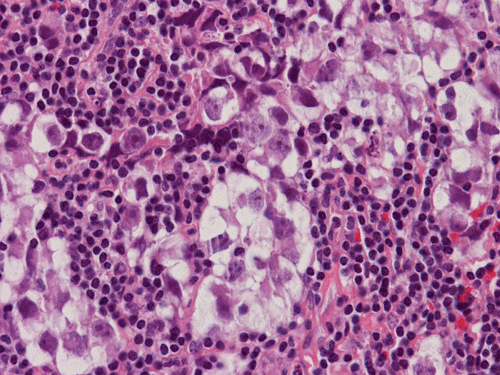

Pathology of the Case: The sample submitted for frozen section has a papillary structure which can be identified as the choroid plexus (Panel C). The center of the choroid plexus is expanded by some large cells accompanied by some smaller cells presumably lymphocytes (Panel D and E). On hematoxylin and eosin stain of the permanent sections, the tumor is composed of clusters of large cells in a background of lymphocytes. On higher magnification, the large cells have enlarged nuclei with prominent nucleoli. No trophoblasts or nor seminomatous component are identified. Immunohistochemistry demonstrated strong positive reactivity for placental alkaline phosphatase (PLAP) (Panel I) and CD117 (c-kit) in the large atypical cells (Panel J). The lymphocytes in the background are strongly immunoreactive for leukocyte common antigen (LCA) (Panel K) but negative for PLAP and CD117.

The discussion here will be limited predominantly to germinoma. Histologically, germinoma has very characteristic features heralded by large, atypical germinoma cells in a background of benign lymphocytes. The germinoma cells are usually huge, with a moderated amount of cytoplasm, and with prominent nucleoli. These cells, even though large, are rarely bizarre. The proportion of germinoma cells with lymphocytes can be highly variable. While most cases show a good mix of both component, the small biopsies yielded by endoscopic biopsy can sample in areas that are lymphocyte predominant or germinoma cell predominant areas which lead to diagnostic pitfalls. It should also be reminded that germinoma has a strong tendency to undergo granulomatous changes. Such granulomatous changes may completely efface the usually big cell-small lymphocyte classic pattern. These biopsies, however, would histologically suggest infection but the clinical history usually would not. Knowing the clinical history is often helpful. Trophoblastic cells could be seen and their presence may indicate a worse prognosis for germinomas. Non-seminomatous component such as embryonal cell carcinoma, yolk sac tumor (endodermal sinus tumor), and choriocarcinoma should also be identified if present.